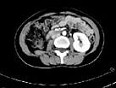

- 多项选择题女,35岁, 右侧腰部不适,CT增强扫描如图所示, 下列说法正确的是 ( )

A、右肾轮廓明显小于左侧,边缘光滑规则

B、左肾代偿性肥大

C、考虑为右小肾畸形

D、右肾完全无功能

E、考虑为右肾肾自截